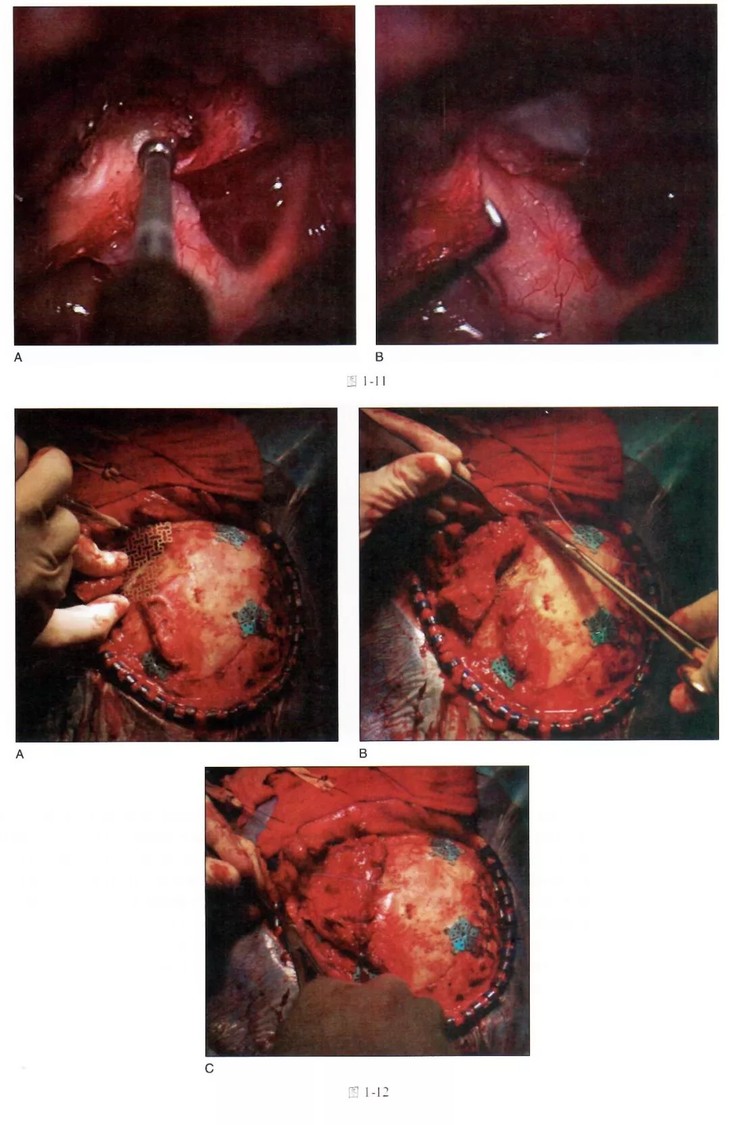

全书涵盖了总论、颅底肿瘤、血管病、功能神外、脊柱脊髓五大方面。由浅入深,既有基本的手术入路,又有最新的术式,按适应证、禁忌证、手术计划、手术经过、大师教诲逐步展开,尤其的大师经验教诲一节,更具实用价值。大量精美图片帮助读者理解和迅速掌握相关的知识要点。

《神经外科手术核心技术(翻译版)》作者均为国际上在相应的亚专业内的代表性人物,其临床经验和体会在本书中得到了充分的表述,对临床医生有重要的指导和指南作用。本书旨在提供一种正规的标准化手术步骤和治疗策略,资料新颖,图文并茂,是一本不可多得的神经外科专科培训教材,原著爱思唯尔出版,全书涵盖了总论、颅底肿瘤、血管病、功能神外、脊柱脊髓五大方面。由浅入深,既有基本的手术入路,又有最新的术式,按适应证、禁忌证、手术计划、手术经过、大师教诲逐步展开,尤其的大师经验教诲一节,更具实用价值。大量精美图片帮助读者理解和迅速掌握相关的知识要点。